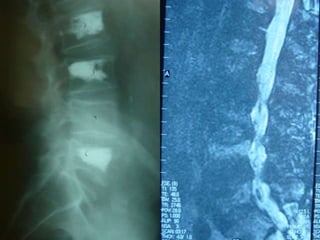

Occult Fracture

75 wm severe! LBP S/P cement 6 months ago